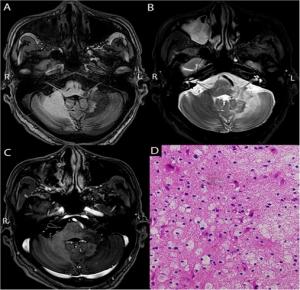

In this study, the researchers aimed to investigate the magnetic resonance imaging (MRI) and pathological characteristics of patients with LCL. Through bone marrow aspiration, they identified 14 cases of acute lymphoblastic leukemia (ALL), one case of chronic lymphoblastic leukemia, six cases of acute myeloid leukemia (AML), and one case of chronic myelomonocytic leukemia (CMML).

The clinical presentation among patients varied widely. Some experienced non-specific symptoms such as headache, vomiting, and limb convulsions, while others showed localized neurological deficits, including blurred vision and limb weakness. Using stereotactic intracranial lesion biopsy, the team found that 13 patients had CNS leukemia (CNSL), while the remaining nine had CNS secondary lesions related to leukemia treatment. These included five cases of CNS infection and four cases of neurodegenerative conditions.

In eight patients, the clinical diagnosis did not align with the biopsy findings. “In one case, the clinical diagnosis pointed to a neurodegenerative disorder, but the biopsy revealed a fungal brain abscess,” explains Dr. Wang. He further adds, “This highlights the limitations of relying solely on clinical or imaging data for diagnosis.”

The researchers also observed that imaging techniques such as cranial CT and MRI lacked sufficient specificity for identifying CNSL. Variability in CSF analysis and overlapping imaging features contributed to misdiagnoses, which in some reports may reach up to 75%. CNSL can be mistaken for a range of conditions, including meningitis, stroke, demyelinating disease, infection, or even Bálint syndrome.